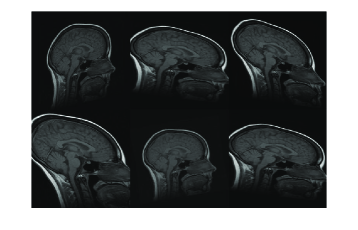

Figure 7: Resulting registration of images with random affine warps. Each row includes source, target and registered source

Refer to caption

In Figure 7, three example registration results of randomly and affinely warped images are shown. The resulting images clearly show that registered source images are in good agreement with target images. Registration quality is measured over 30 randomly deformed images by mean of the square of the differences in intensity (MSE). Experiment has been done both in image scale and on standard scale to show improvement in MSE sense. Table-1 shows the MSE, maximum MSE and minimum MSE over 30 registration examples on image scale and on intensity scale respectively.